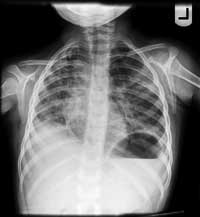

Her follow-up CXR is shown below. It shows a shrinking right lung with continued bilateral opacifications.

CXR

from Aug 24